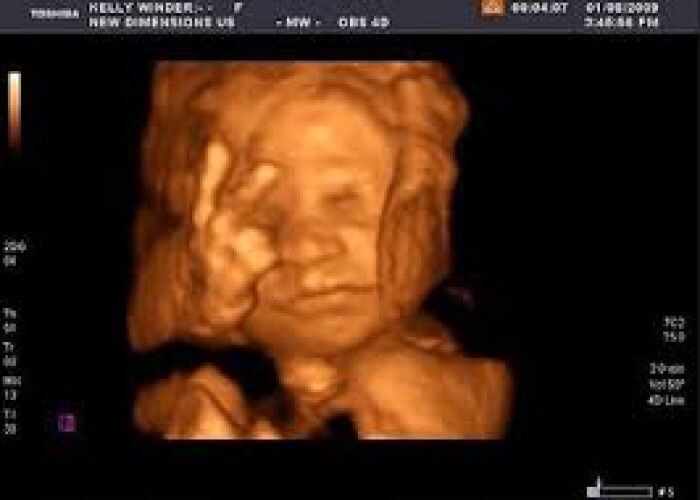

Tak wajib tapi penting untuk kita tau perkembangan baby, x mahal pun. Saya suggest klinik sono. 18w keatas dah boleh scan details. Nak lagi gempak 24w keatas boleh scan 5d 🤗

dia tak la wajib, tapi kalau buat detail scan, boleh detect abnormal pada baby mcm jantung dia x sempurna ke, buah pinggang dia bengkak ke. yg saya tahu mcm tu lah